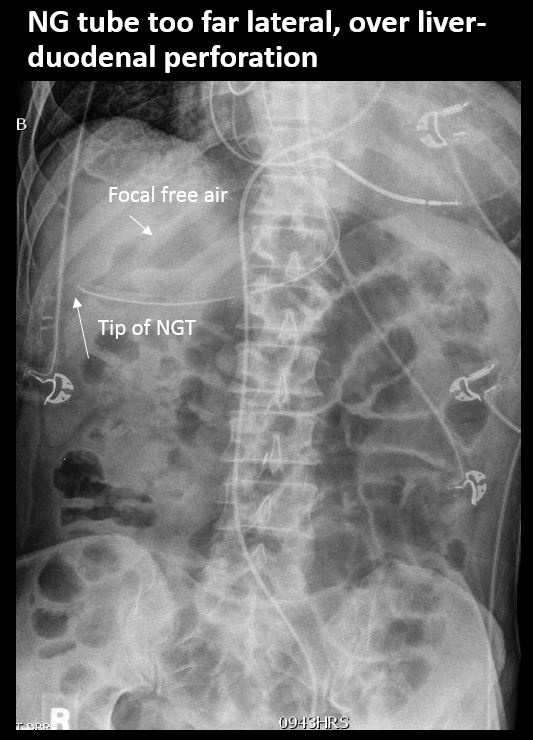

There is an NG/OG tube in place and properly positioned (the tip or sideport of the NG/OG tube is NOT above the GE junction and is NOT beyond the pyloris or otherwise malpositioned). [Yes/No]

There is scattered extraluminal air or an abnormal focal collection of air in the abdomen or pelvis. [Yes/No]